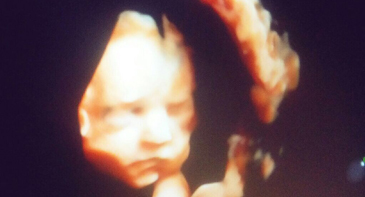

Peşəkar Radioloq Dr.Arzu Cəfərova ekstrakranial və aşağı,yuxarı ətrafların doppler müayinəsini həyata keçirir və bildirir ki, Dopplerometriya ...